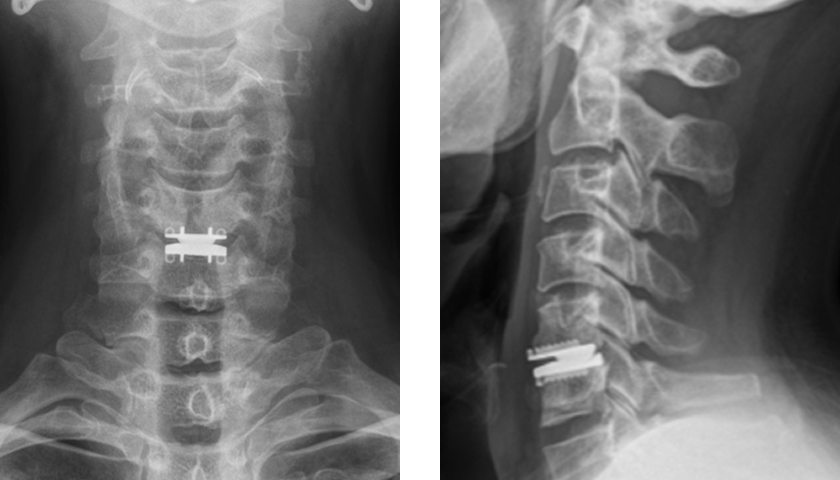

前方除圧固定術

突出した椎間板や骨棘を前方から除去して固定

椎間板を摘出し、チタンケージや人工骨で固定